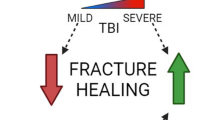

The peripheral nervous system, as recent research has highlighted, plays a fundamental role in the physiological process of fracture healing, actively influencing a wide range of cellular and molecular events (Fig. 1). The impetus for deepening this understanding is twofold: scientific and clinical. The development of novel drugs targeting aspects of the nervous system could potentially enhance the speed and quality of fracture healing, alleviate complications associated with fractures such as pain, and decrease the burden on healthcare systems.

Nervous system regulation of fracture healing. This figure summarizes the contributions of the various aspects of the nervous system to fracture healing that were emphasized in this review. Growth factors and neuropeptides, including substance P (SP), calcitonin gene-related peptide (CGRP), and neuropeptide Y (NPY), all exert positive influences on fracture healing. The sympathetic nervous system, which releases norepinephrine (NE), can positively or negatively impact fracture healing depending on the degree of its involvement; local sympathectomies may improve fracture healing, while total systemic sympathetic denervation impairs fracture healing. Created with BioRender.com